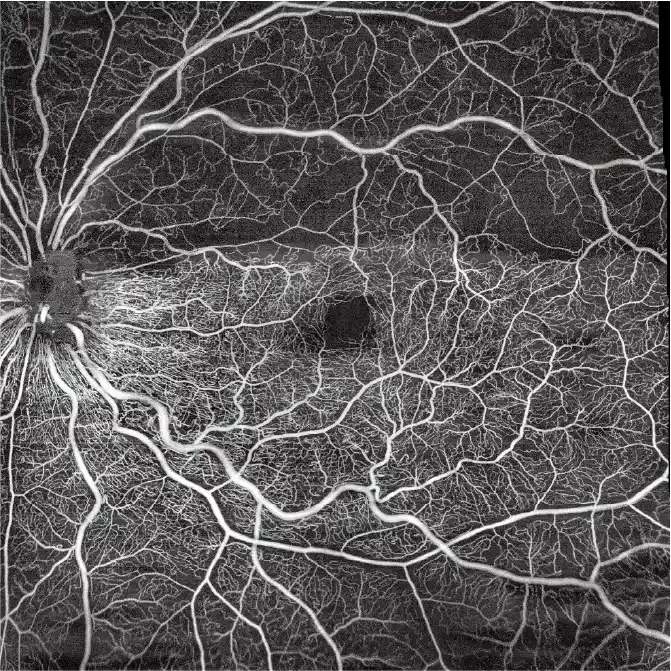

Angiografia

OCTA

Maks. pojedynczy skan (posterior)

15×15 mm

Maks. pojedynczy skan (anterior)

18×18 mm

Maks. rozdzielczość (pojedynczy skan)

1024×1024

Kwantyfikacja przepływu krwi

Pomiar przepływu krwi w siatkówce, naczyniówce, tarczy nerwu wzrokowego i segmencie przednim